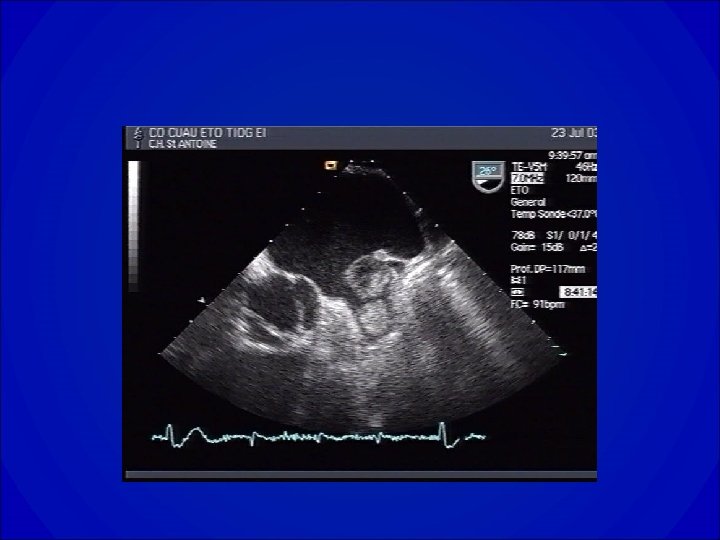

Echocardiogramme dans la RAo • Confirme un diagnostic clinique: épaississement ou calcification des valves dont l’ouverture est diminuée. • Apprécie le degré: gradient et surface (équation de continuité ou planimétrie en ETO). • Donne des renseignements étiologiques. • Apprécie le retentissement VG ( hypertrophie, fonction systolique et diastolique). • Recherche une valvulopathie associée et ou une pathologie de l’aorte ascendante.

Echo du RAo

Diagnostic • ECG ACFA, Surcharge auriculaire gauche, Signes d’atteintes VG (HVG, Ondes Q…. ) • Radiographie de thorax= dilatation du VG • ETT +/- ETO -Confirmation et quantification de la fuite -Faisabilité d’une réparation chirurgicale (plastie) -Évaluation du retentissement VG -Lésions associées ?

Diagnostic • SYMPTOMES – Dyspnée – Roulement diastolique mitral • ECG – ACFA, Surcharge auriculaire gauche, • ETT +/- ETO – Confirmation et quantification de la sténose – Faisabilité d’une réparation percutanée ou chirurgicale (plastie) – Lésions associées ?